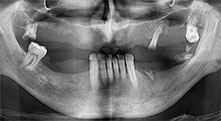

Брату: Ние използваме инструментите за събиране на костни блокове и разделяне на алвеоларни гребени. Ние също използваме Piezomed B6/B7 за остеотомия на наранени зъби и отстраняване на неуспешни импланти. Всички индикации, които изискват дълбоки, чисти разрези.

Брату: Смятам, че пиезохирургията е огромна крачка напред в оралната хирургия. Тази техника прави препарацията на кост много по-безопасна и по-лесна. Загубата на кост е малка, например при екстракции. Това е много важно в естетичната зона, особено ако е планирано имедиатно имплантиране. Пиезохирургията е по-безопасна за меките тъкани: нараняването на мембраната в синуса е вече в историята, както и засягането на нервите при събиране на костни блокове. Данните сочат намалено постоперативно подуване и болка. Пиезохирургията също е перфектна за препарация на синусните прегради. И накрая, но не на последно място, нашите пациенти се радват на атравматичния характер на тази технология.

Вашата болница в Тимишоара предлага орална хирургия и протетично възстановяване с акцент върху имплантологията. Използвате ли Вашия апарат Piezomed за други индикации?